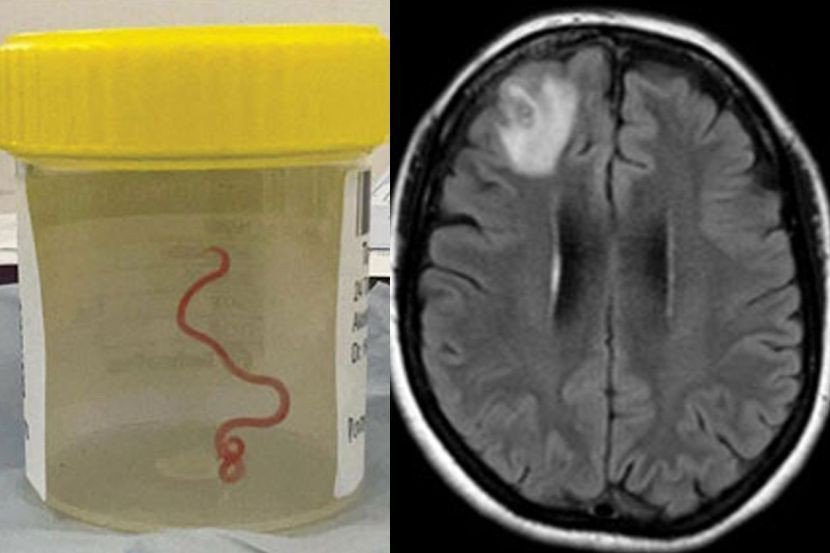

Cacing parasit sepanjang 8 sentimeter itu dikeluarkan dari otaknya menerusi satu pembedahan.

Imbasan pengimejan resonans magnetik (MRI) terhadap otaknya mendapati terdapat helminth motil iaitu cacing gelang parasit yang hidup di lobus hadapan kanan otaknya.

Pembedahan merupakan satu-satunya pilihan, dan doktor berjaya mengeluarkan cacing gelang yang berukuran 8 sentimeter panjang dan diameter 1 milimeter diameter.